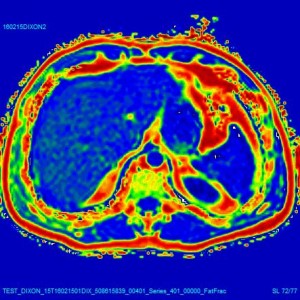

Anche il metodo Dixon (2 o 3 punti) richiede una poco veloce acquisizione di immagini “in fase” ed “in opposizione di fase” per ottenere immagini acqua/grasso, e quindi in definitiva solo una valutazione “qualitativa” del contenuto di grasso nel fegato.

I ricercatori della QMRI Tech hanno sviluppato un tecnica che consente una misura RM “quantitativa” del contenuto di grasso nel fegato, in particolare una misura della densità protonica della frazione di grasso (“Proton Density Fat-Fraction”). La tecnica comprende un appropriato protocollo di imaging con sequenze RM dedicate ed un software di elaborazione delle immagini progettato e realizzato appositamente.

Questa tecnica “quantitativa” molto avanzata utilizza un metodo cosiddetto “multi-echo”, “multi-peak” in una singola acquisizione in “breath-hold”, tenendo quindi conto della complessità dello spettro RM del grasso epatico (“Complex-based Chemical Shift Technique”). *